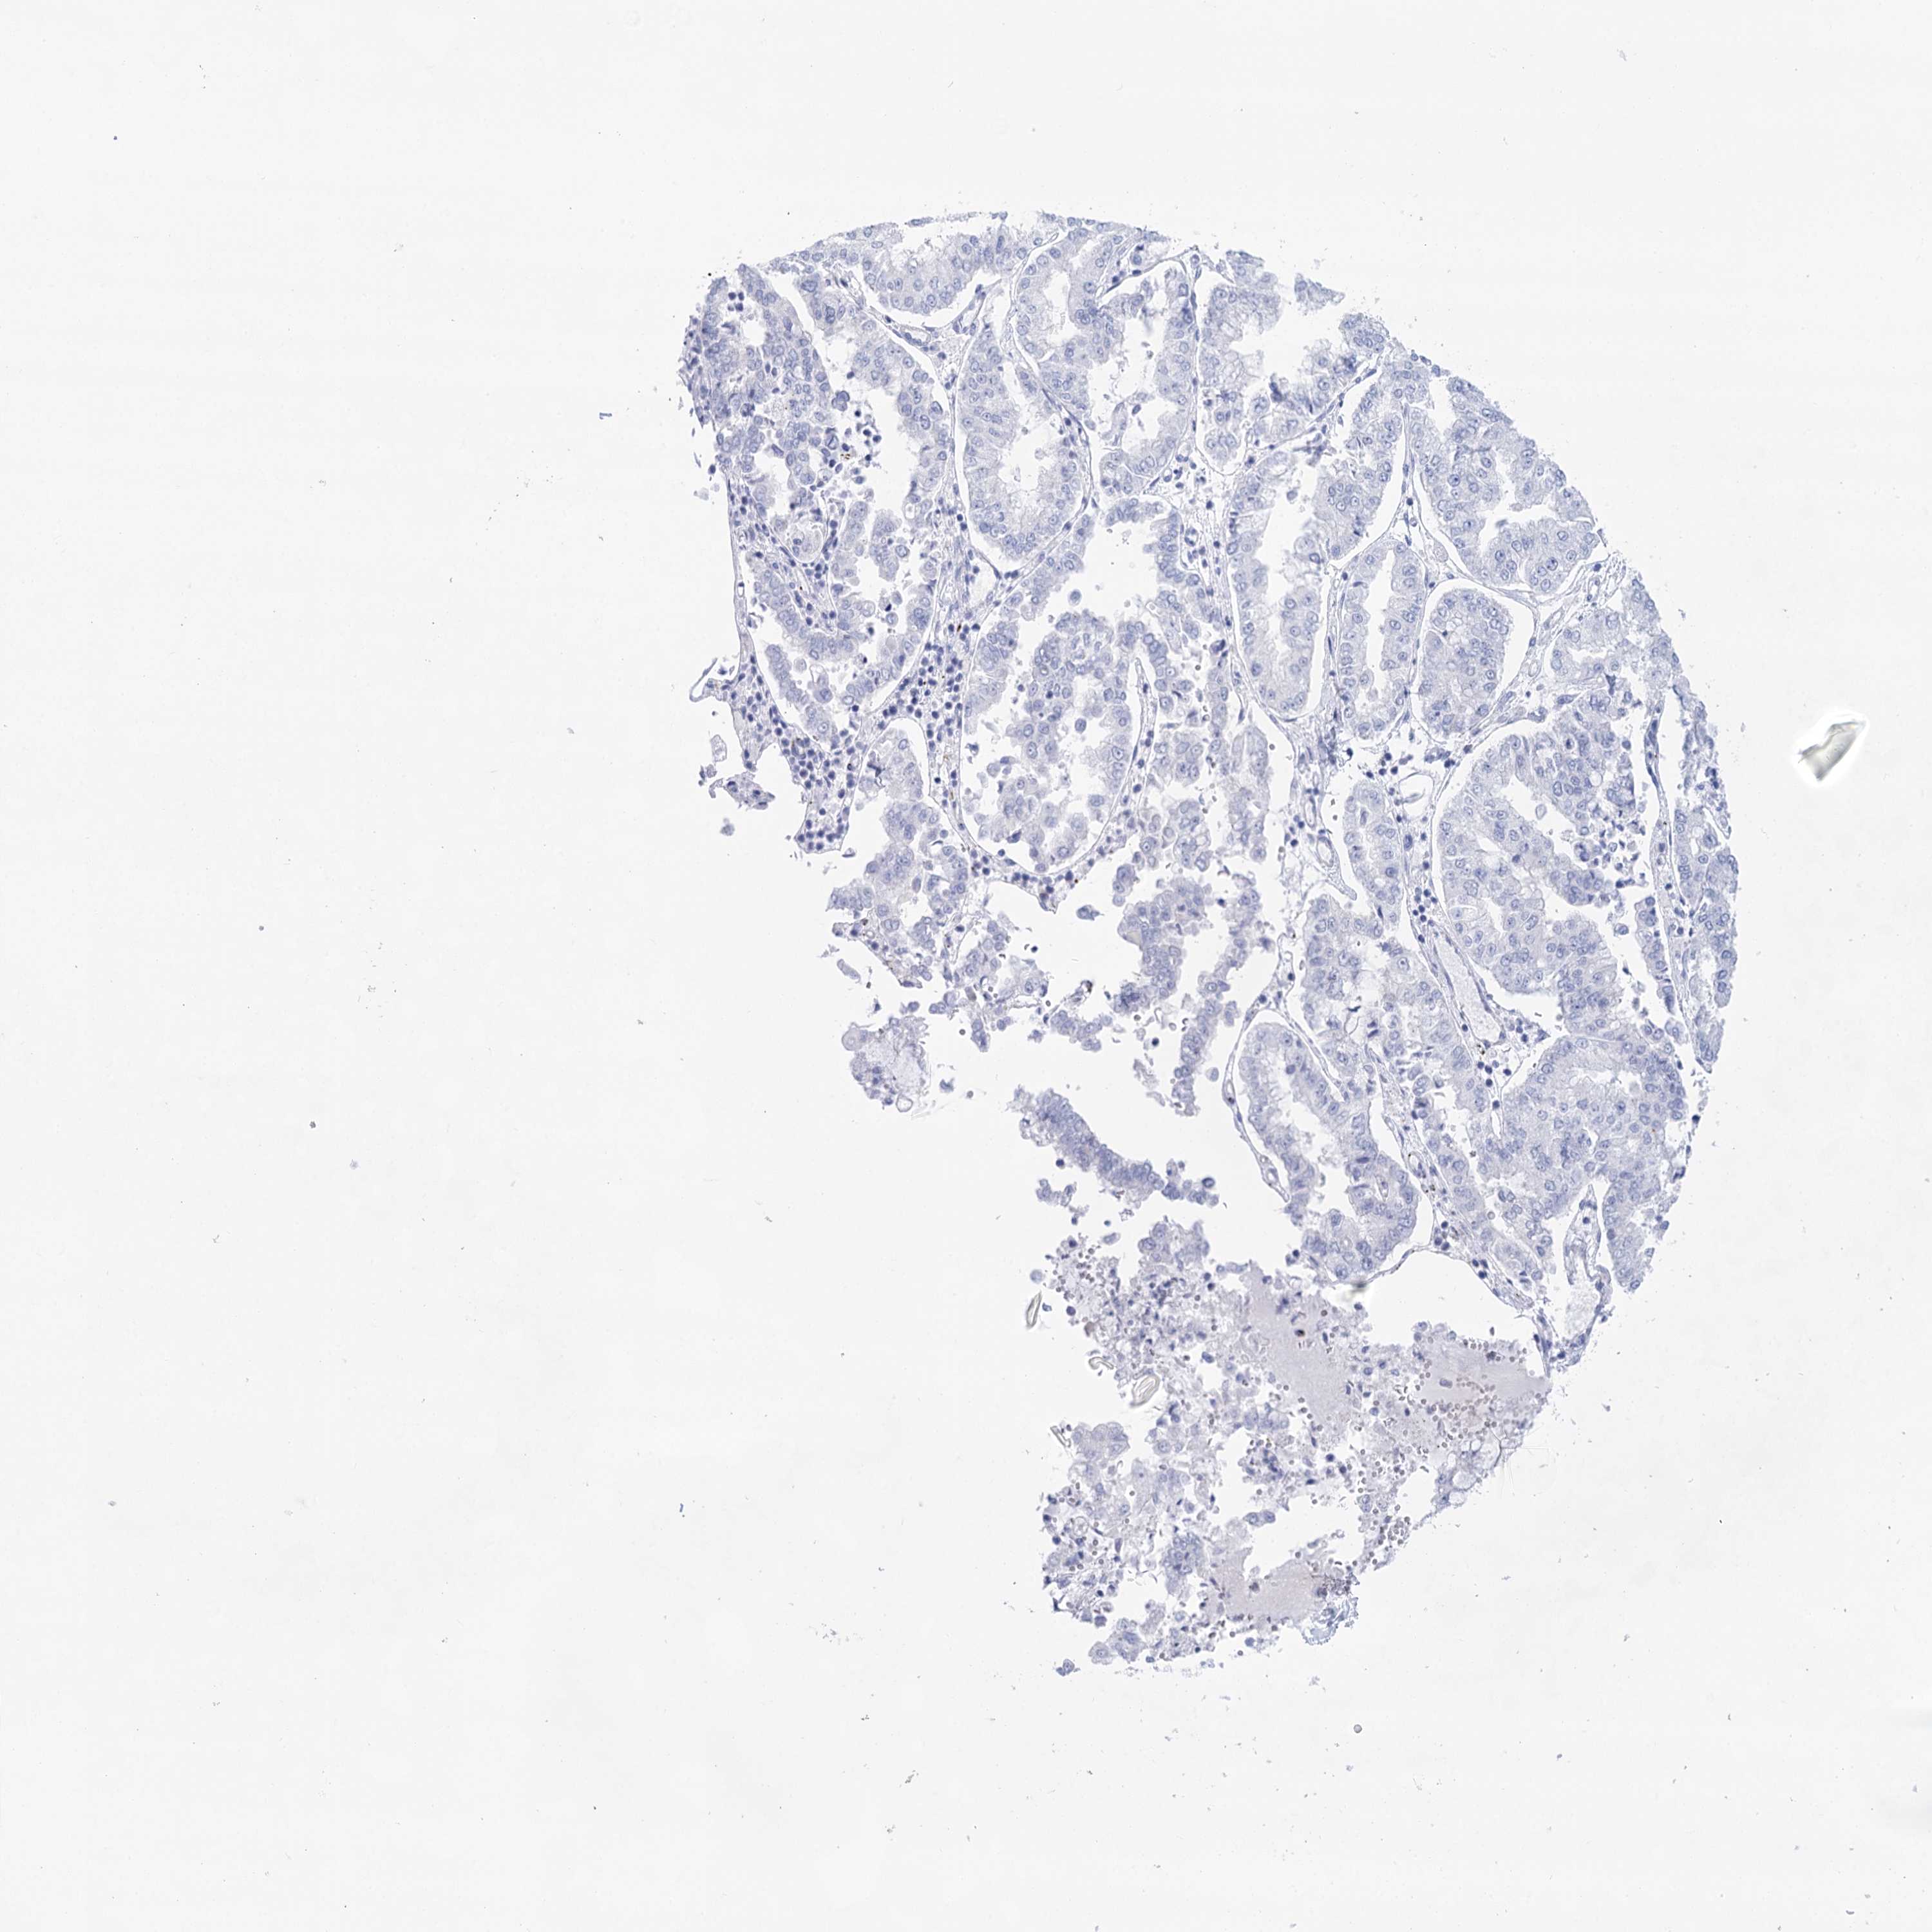

STOMACH CANCER - Protein expressioni

A mouse-over function shows sample information and annotation data. Click on an image to view it in a full screen mode. Samples can be filtered based on level of antibody staining by selecting one or several of the following categories: high, medium, low and not detected. The assay and annotation is described here.

Note that samples used for immunohistochemistry by the Human Protein Atlas do not correspond to samples in the TCGA dataset.

Antibody stainingi

Antibody staining in the annotated cell types in the current human tissue is reported as not detected, low, medium, or high, based on conventional immunohistochemistry profiling in selected tissues. This score is based on the combination of the staining intensity and fraction of stained cells.

Each image is clickable and will lead to virtual microscopy that enables deeper exploration of all samples and also displays staining intensity scores, fraction scores and subcellular localization as well as patient and tissue information for each sample.

Antibody HPA029855

Antibody HPA029856

Antibody CAB026343

Staining

High

Medium

Low

Not detected

Intensity

Strong

Moderate

Weak

Negative

Quantity

>75%

75%-25%

<25%

None

Location

Nuclear

Cytoplasmic/membranous

Cytoplasmic/membranous,nuclear

Adenocarcinoma, NOS